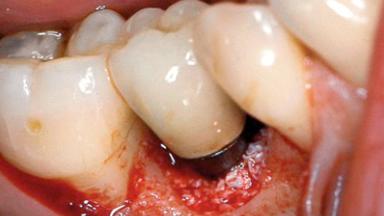

A 30-year-old female patient was referred to the Department of Periodontology of the University of Bern, Switzerland, by a dentist in private practice. Tooth 45 had been congenitally missing and had been replaced with a titanium implant three years prior to the first visit at the Department of Periodontology. The tissue level implant had a diameter of 4.1 mm, a length of 12 mm, and a sandblasted and acid-etched (SLA) surface (Straumann® Dental Implant System; Institut Straumann AG, Basel, Switzerland). The metal-ceramic crown on implant 45 had been cemented permanently. Implant 45 had been diagnosed with peri-implantitis by the referring dentist in the course of regular supportive care.